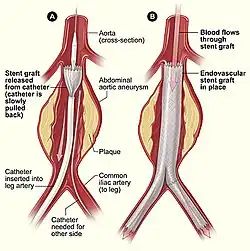

Endovaskuläre Therapie des Bauchaortenaneurysmas

Ein alternatives Verfahren zur offenen konventionellen Operation ist die endovaskuläre Aneurysmatherapie (EAT oder EVAR für endovascular aneurysm bzw. aortic repair) durch Aneurysmaexklusion mittels Aortenstent. Dieser wird über die Femoralgefäße nach proximal in die Aorta platziert und so das Aneurysma ausgeschaltet. Seit der ersten EAT durch Parodi 1991 liegen Erfahrungen mit dieser wenig invasiven Methode bei mehreren tausend Patienten vor. Die publizierten Daten schwächen die anfängliche Euphorie für diese Methode ab. Es zeigt sich einerseits, dass die Platzierung bei einem Großteil der Patienten primär erfolgreich verläuft. Andererseits sind die Systeme keineswegs ausgereift, so dass im Mittel- und Langzeitverlauf die Komplikationsrate nicht unbeträchtlich ist.

Die endovaskulären Prothesensysteme bestehen aus einem selbstexpandierenden Nickel-Titan (= Nitinol)-Skelett, das von einer dünnwandigen Polyester- oder PTFE-Prothese überzogen ist. Dieses System wird auch Stentgraft, Hybridprothese oder gecoverter Stent genannt. Am gebräuchlichsten und in der elektiven Situation fast ausschließlich gebraucht sind modular aufgebaute Bifurkationsprothesen. Das Hauptmodul besteht aus dem Prothesenkörper, einem langen und einem zweiten kurzen Schenkel. Letzterer wird mit einem gesonderten kontralateralen Schenkel ergänzt. Beide Komponenten sind in getrennten Entladungssystemen verpackt. Sie werden über eine Inzision der Leistenarterie eingeführt, unter Röntgendurchleuchtung in das Aneurysma platziert und expandiert. Es sind auch aorto-uni-iliakale Systeme erhältlich, bei welchen die Blutversorgung des kontralateralen Beines über einen Crossover-Bypass erfolgt. Postinterventionell kann der Patient nach einem kurzen Aufenthalt auf der Überwachungsstation auf die Normalstation verlegt werden. Die Entlassung erfolgt nach Kontrolle bezüglich Endoleak (Duplexsonografie und CT) ca. vier Tage nach der Operation. Im Gegensatz zur offenen Operation, bei welcher kaum Nachkontrollen nötig sind, liegt das große Problem der Endoprothesen in der Entwicklung von so genannten Endoleaks (Leckage), die in bis zu 44 % der Fälle auftreten. Durch Endoleaks kommt der Aneurysmasack wieder unter systemischen Blutdruck, so dass das Ziel der Operation nicht erreicht ist. Folgende Endoleaktypen werden unterschieden:[2]

- Typ I wird durch eine undichte proximale oder distale Andockstelle verursacht. Es sollte so bald wie möglich endovaskulär mittels Verlängerung des Stents nach proximal oder offen operativ korrigiert werden.

- Endoleaks vom Typ II sind Folge eines retrograden Flusses von aortalen Seitenästen (Lumbalarterien/AMI). Sie kommen bei bis zu 40 % vor und können durch selektive Embolisation angegangen werden, verschließen sich jedoch in ca. 50 % spontan. Obwohl Aneurysmarupturen wegen Typ-II-Endoleaks beschrieben sind, scheinen sie das Rupturrisiko in größeren Serien innerhalb von zwei bis drei Jahren nicht zu beeinflussen.

- Typ-III-Endoleaks werden durch Graftdefekte oder Diskonnektion der Module verursacht. Ihnen wird eine Erhöhung des Rupturrisikos zugeschrieben; eine sofortige Sanierung ist empfehlenswert.

- Typ IV ist selten und beruht auf der Porosität des Grafts. Nach heutigem Wissen können auch nach einigen Jahren noch Endoleaks auftreten, die behandlungsbedürftig sind. Aus diesem Grund ist eine mindestens jährliche Nachkontrolle mittels Duplexsonografie, MRT oder CT notwendig. Die Langzeitresultate dieses Verfahrens sind noch völlig unbekannt.